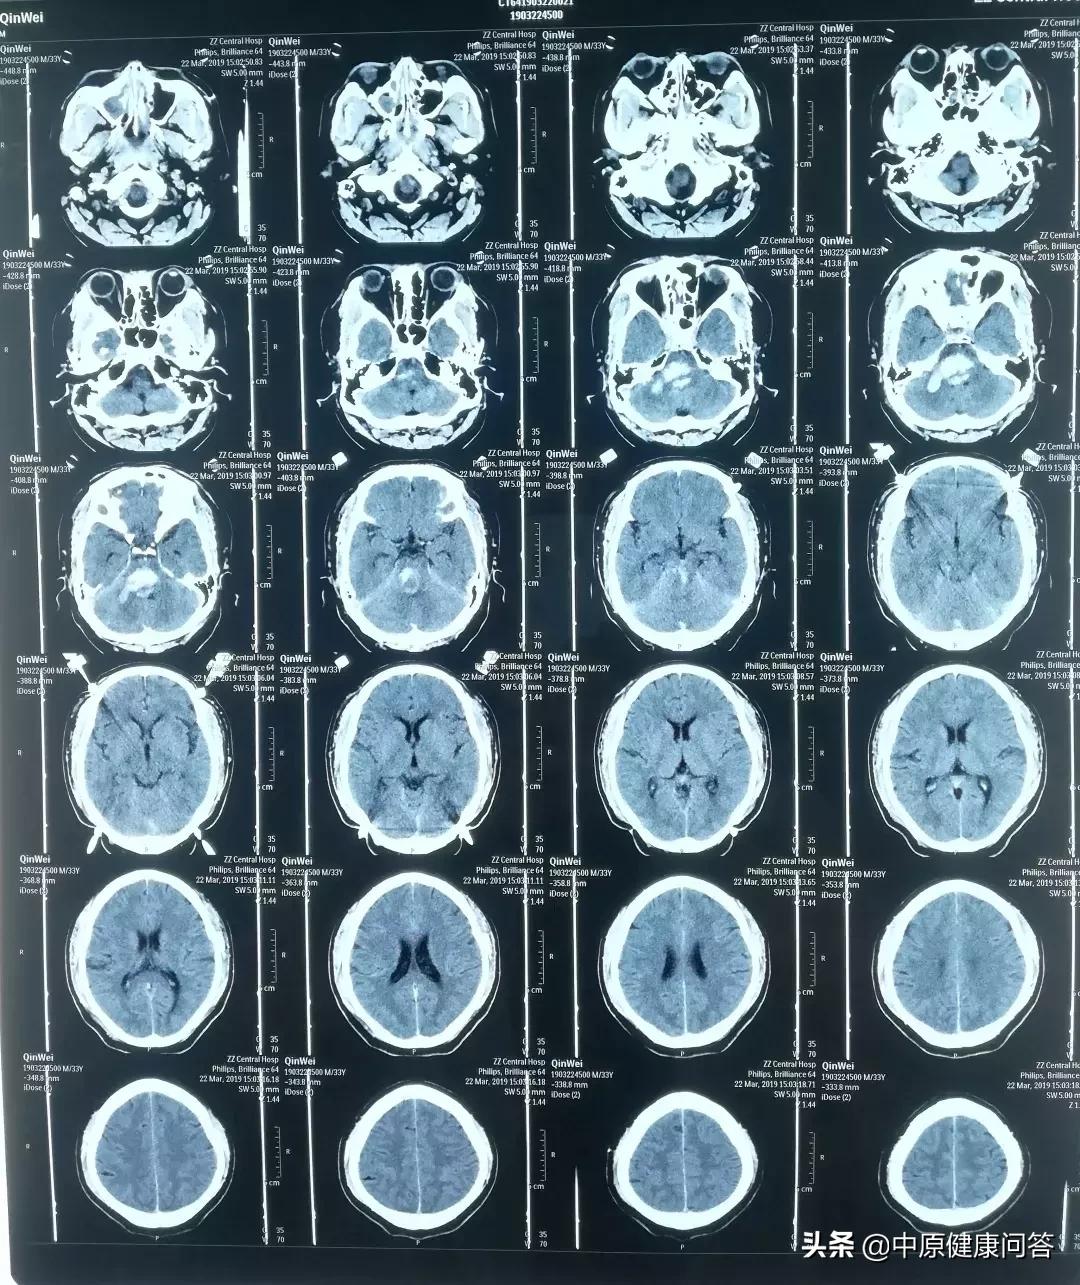

“入院后,进行了CT检查,显示患者脑干及右侧桥臂脑出血、蛛网膜下腔出血,出血量约10ml......当时就给予了患者气管插管,呼吸机辅助呼吸,病情情况危重,生存希望渺茫。”接诊的急诊科医生回忆说。

术后复查,患者血肿清除彻底,生命体征稳定。